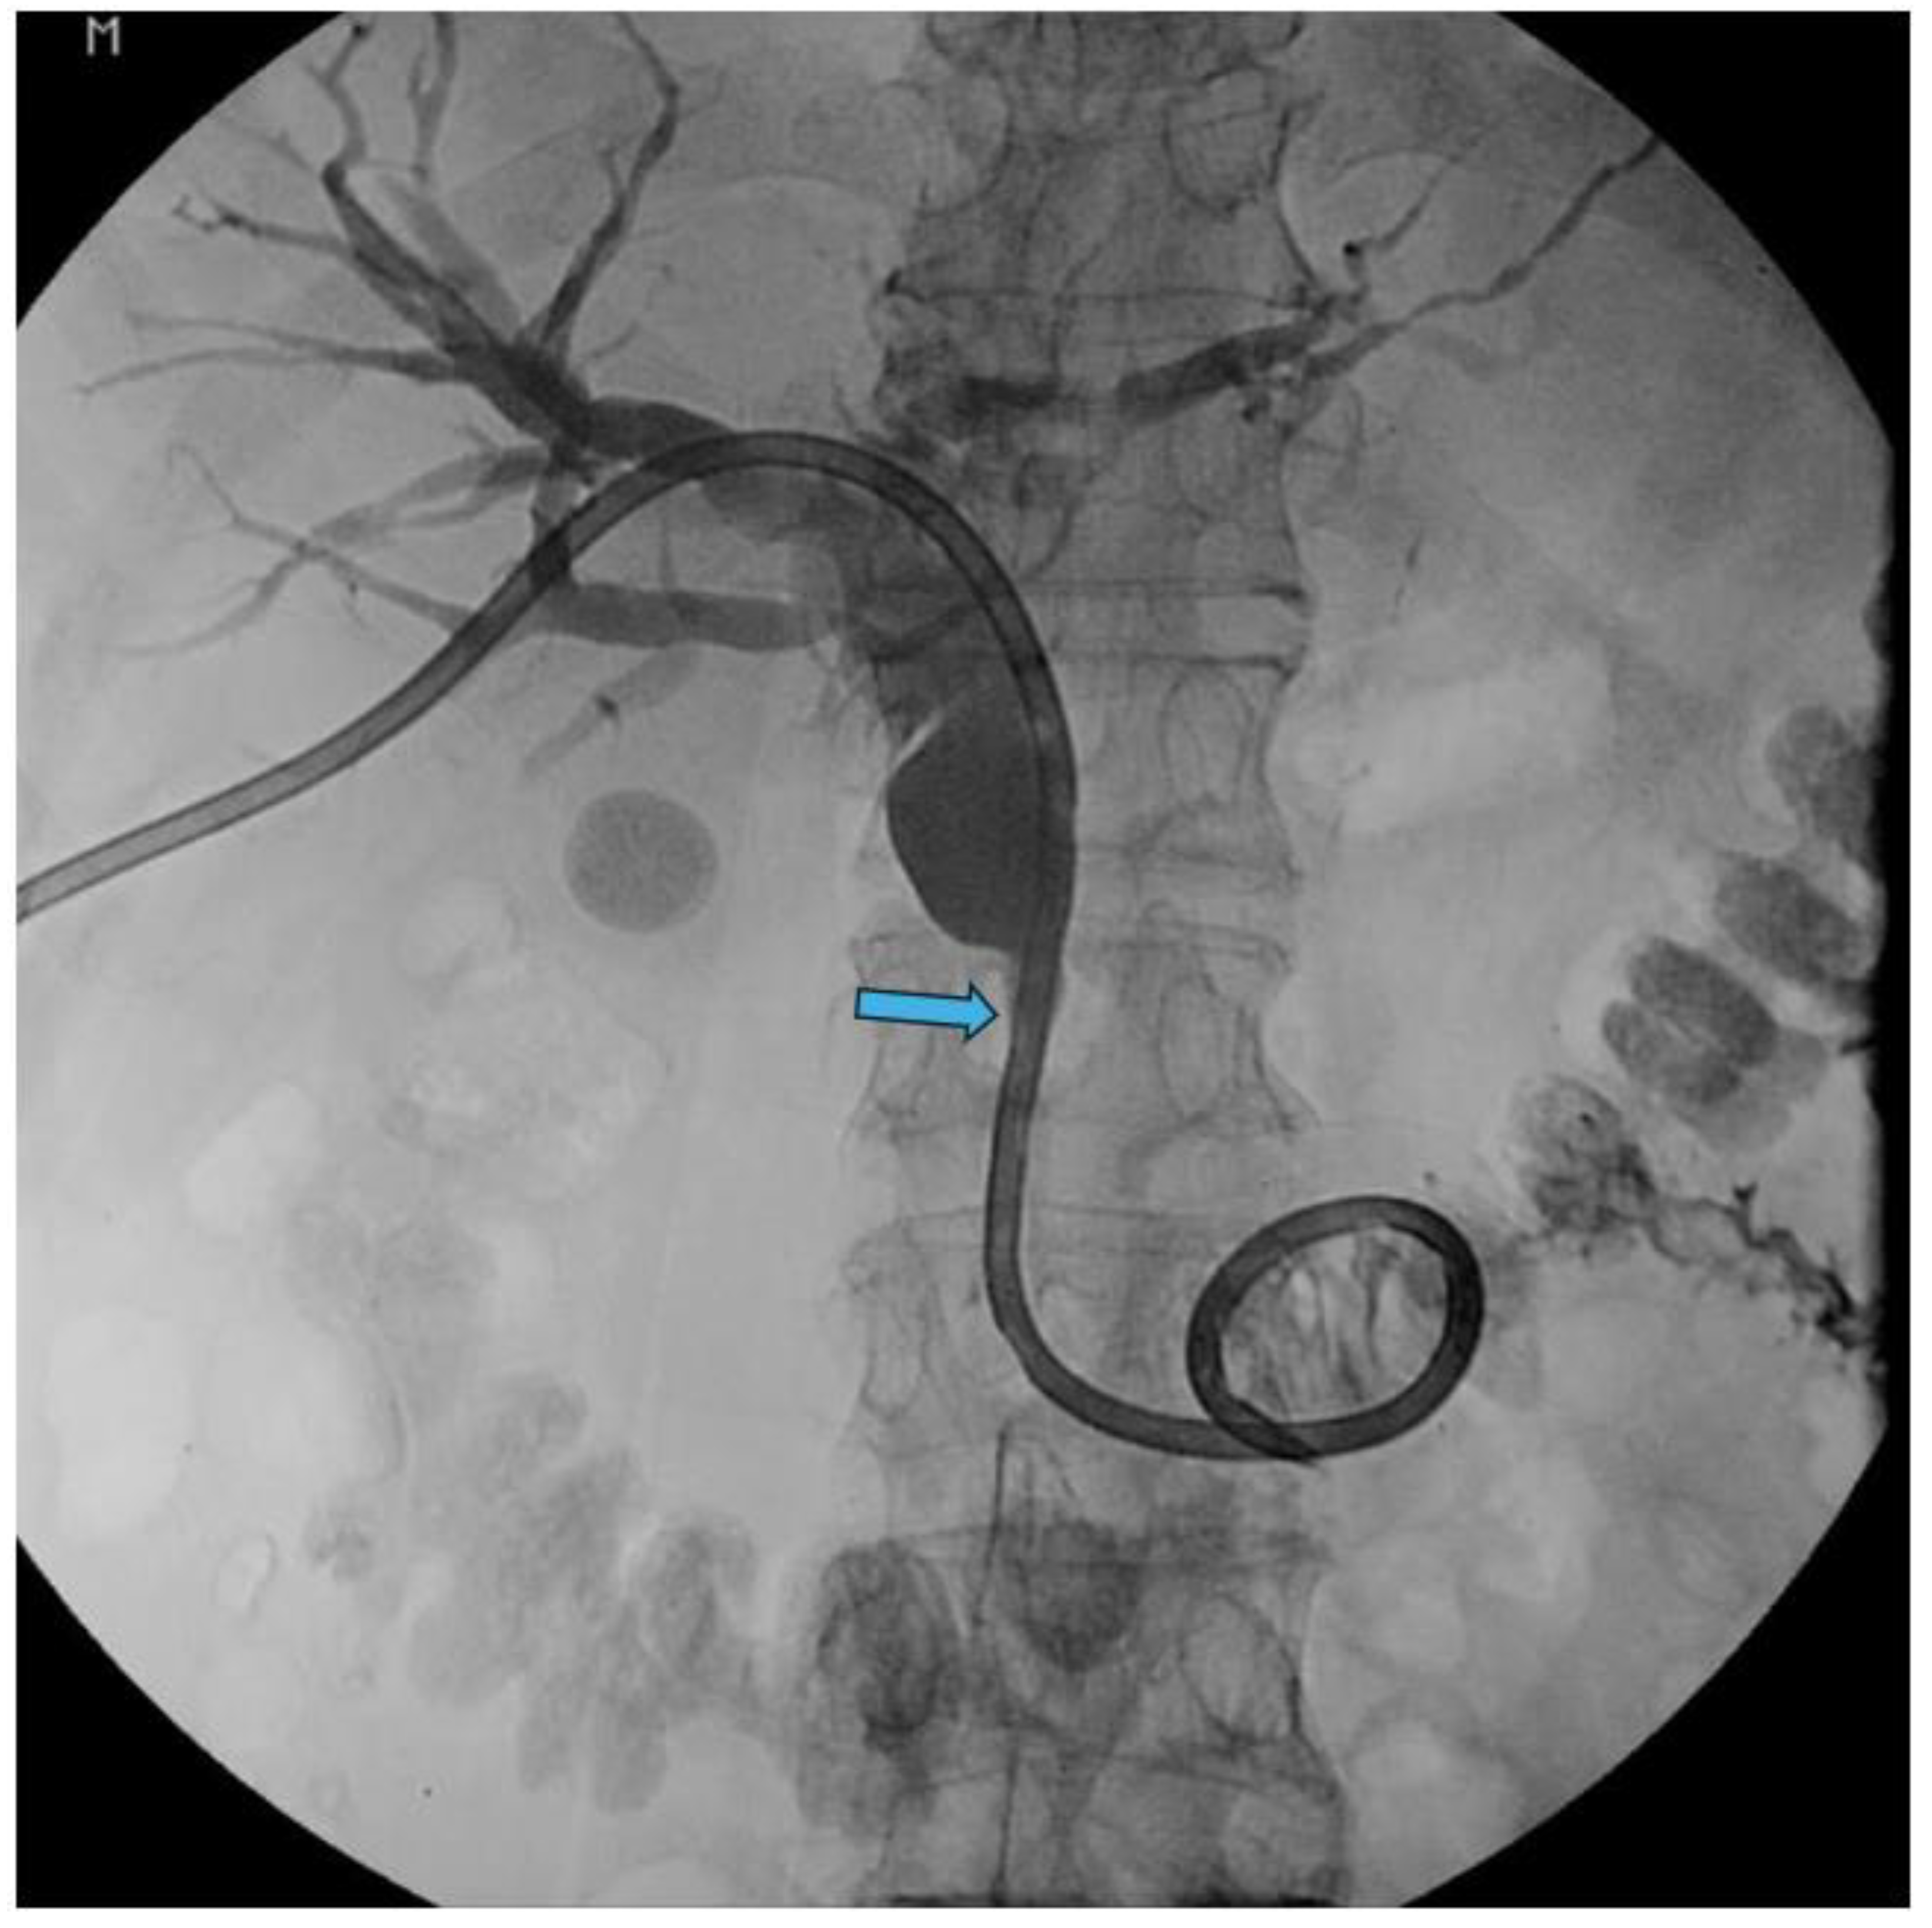

Pancreatic cancer is an aggressive malignancy, and the current 5-year survival rate in the United States, according to the Surveillance, Epidemiology, and End Results Program data, approximates 12%. Although the current standard for resectable pancreatic cancer most commonly includes neoadjuvant chemotherapy prior to a curative resection, surgery in the majority of patients has historically been palliative. The latter interventions include open or laparoscopic bypass of the bile duct or stomach in cases of obstructive jaundice or gastric outlet obstruction, respectively. Non-surgical interventional therapies started with percutaneous transhepatic biliary drainage (PTBD), both as a palliative maneuver in unresectable patients with obstructive jaundice and to improve liver functions in patients in whom surgery was delayed. Likewise, interventional radiologic techniques included placement of plastic and ultimately self-expandable metal stents (SEMS) through PTBD tracts in patients unresectable for cure as well as percutaneous cholecystostomy in patients who developed cholecystitis in the context of malignant obstructive jaundice. Endoscopic retrograde cholangiopancreatography (ERCP) and stent placement (plastic/SEMS) was subsequently used both preoperatively and palliatively, and this was followed by, or undertaken in conjunction with, endoscopic gastro-duodenal SEMS placement for gastric outlet obstruction. Although endoscopic ultrasound (EUS) was initially used to cytologically diagnose and stage pancreatic cancer, early palliation included celiac block or ablation for intractable pain. However, it took the development of lumen-apposing metal stents (LAMS) to facilitate a myriad of palliative procedures: Cholecystoduodenal, choledochoduodenal, gastrohepatic and gastroenteric anastomoses for cholecystitis, obstructive jaundice, and gastric outlet obstruction, respectively. In this review, we synopse these procedures which have variably supplanted surgery for the palliation of pancreatic cancer in this rapidly evolving field.

Interventional Radiology Palliation